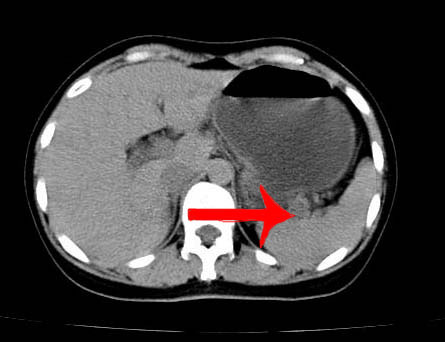

以下是引用guzhongliangddd在2006-11-9 17:55:00的发言:[br]请重点讨论图中箭头所示{脾门部,我首先考虑的是1:血管结构2:胰尾组织??)[br][br][本贴已被 guzhongliangddd 于 2006-11-9 18:01:50 修改过]

以下是引用西北偏北在2006-11-9 20:15:00的发言:[br]箭头所指结构边缘不光整,不支持副脾,考虑胰尾容积层面或血管,做个增强吧.